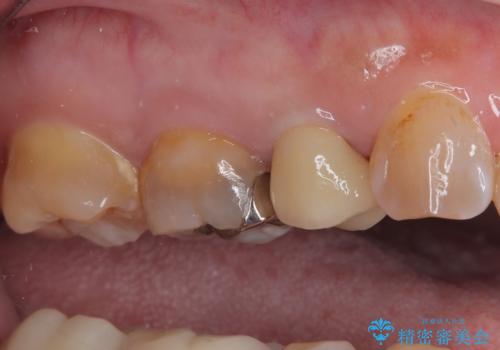

銀歯を外したところ、土台にほとんどむし歯はなかったため、土台のやり替えを行うことなく、セラミッククラウンを装着しました。

セラミック治療の注意事項(リスク・副作用など)

- 天然歯を削ります

- 硬い素材は天然歯を傷つけてしまう場合があります

- かみ合わせや歯ぎしりが強すぎる方はセラミックが割れてしまう可能性があります

- 自費診療(保険適用外治療)となります